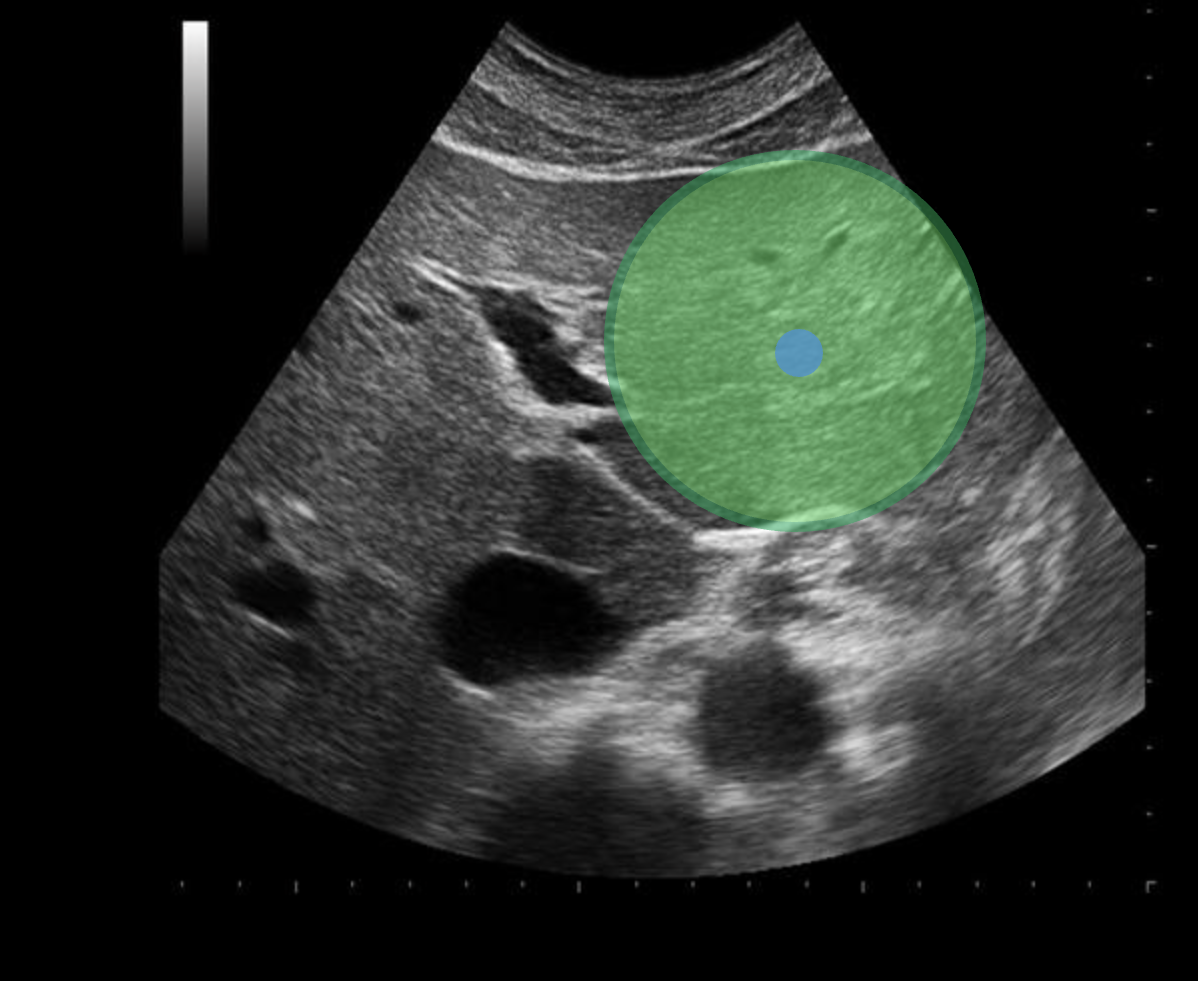

Use your mouse to place your cursor over the center of the lateral left lobe of the liver and click to mark the structure

Use your mouse to place your cursor over the main lobar fissure and click to mark the structure.